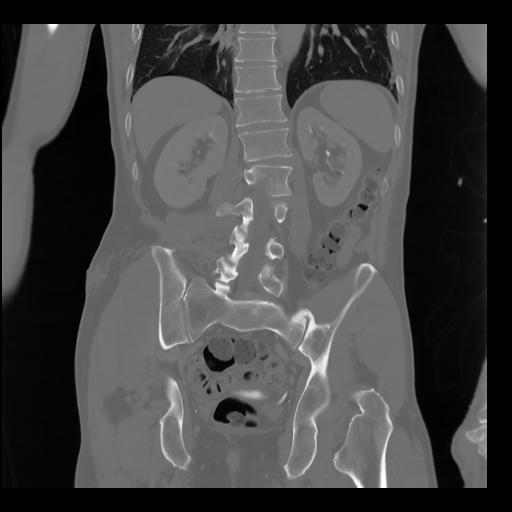

35 CUERPO,CE,Coronal,3.000,CUERPO,Coronal,